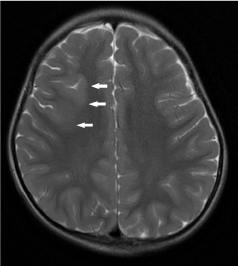

On T1-weighted images, non myelinated white matter is hypointense relative to cortical grey matter, providing a good contrast between cortical grey matter and subcortical white matter. However, between 4 to 8 months of age, gray matter and incompletely myelinated subcortical white matter are almost equal in signal intensity, resulting in blurring of the grey-white matter junction as well as pseudo-thickening of the cerebral cortex. One should not mistake this for MCD. During this period, the cortical ribbon is better depicted on T2-weighted images (Figure 15 a,b).

Figure 15. Pseudo-thickening of the cerebral cortex. (a) Axial T1-weighted image shows blurring of the grey-white matter junction in a 6-month old child. Between 4 to 8 months of age, gray matter and incompletely myelinated subcortical white matter are almost equal in signal intensity, resulting in blurring of the grey-white matter junction as well as pseudo-thickening of the cerebral cortex. (b) Axial T2-weighted image better delineates the grey-white matter junction in this age group.